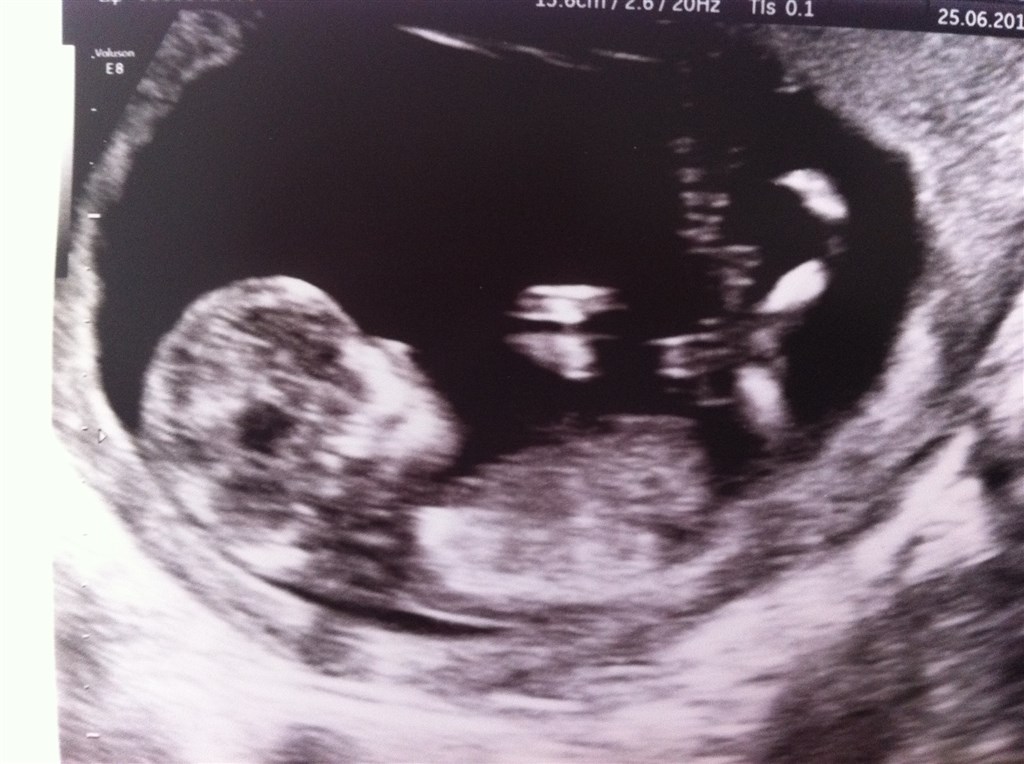

Det er så dejligt det er overstået! Jeg var totalt anspændt indtil jeg så den sprælle på skærmen!

Vi har tid til kønsscanning d. 17.